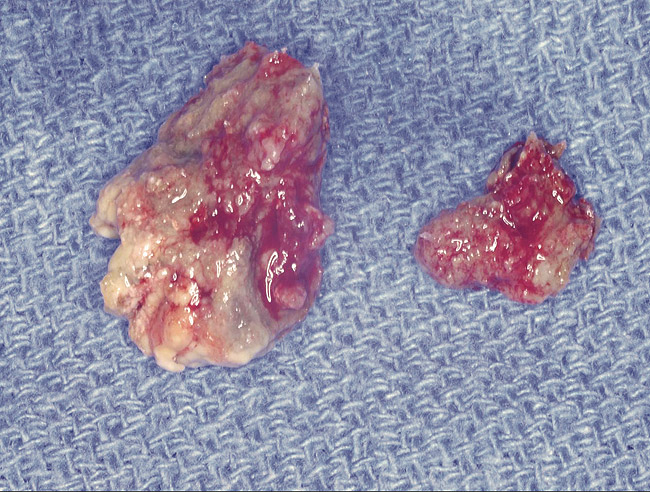

As stated earlier, spontaneous osteonecrosis is also possible. Figure 14 shows a case of spontaneous BRONJ resulting from wearing an ill-fitting denture. The patient had noticed the foreign material, but chose not to act on it. When the material was removed in the dental office (Figure 15 and Figure 16), blood streamed from the nose so severely that the patient had to be sent to an ear, nose, and throat (ENT) physician. The ENT took a computed tomography scan, which showed a large radiolucency in the upper left quadrant where the foreign material once had been (Figure 17). A review of the radiograph (Figure 18) showed that bone in the maxillary arch had decreased mineral density compared with the mandible. The biopsy report found necrotic bone with organisms consistent with actinomyces. These findings were consistent with biopsies found in the literature.22 When the patient returned for a 1-week follow-up, she still had signs of infection and the site had a foul odor and a discharge (Figure 19). The patient was informed that she should follow up with the ENT and return to the dental office after the infection had been resolved.

Figure 16  Necrotic bone.

Figure 16